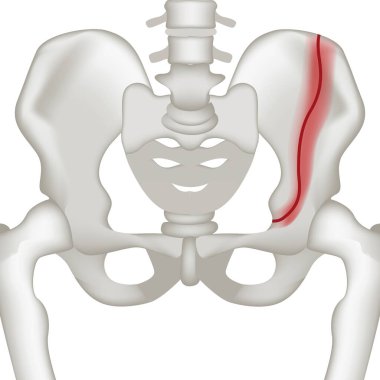

Tıbbi konsept 3 boyutlu illüstrasyon için insan kadın kas anatomisi

KasBileşenlerDorsalfleksörPalmarbrachiiBrevisLongusabdüktöradductorekstansiyonOrasına3d oluşturma3B illüstrasyonCarpiteresdeltoideusDigitorumbrachioradialiskomplikasyondigitiquintipollicisprofundusulnarispronatorPalmarisinterosseiopponenscoracobrachialisKas Anatomisilongus muscleinterossei musclebrevis musclelummbrical muscletricep mucslepollicis musclesuperficialis muscleBenzer İçerikler